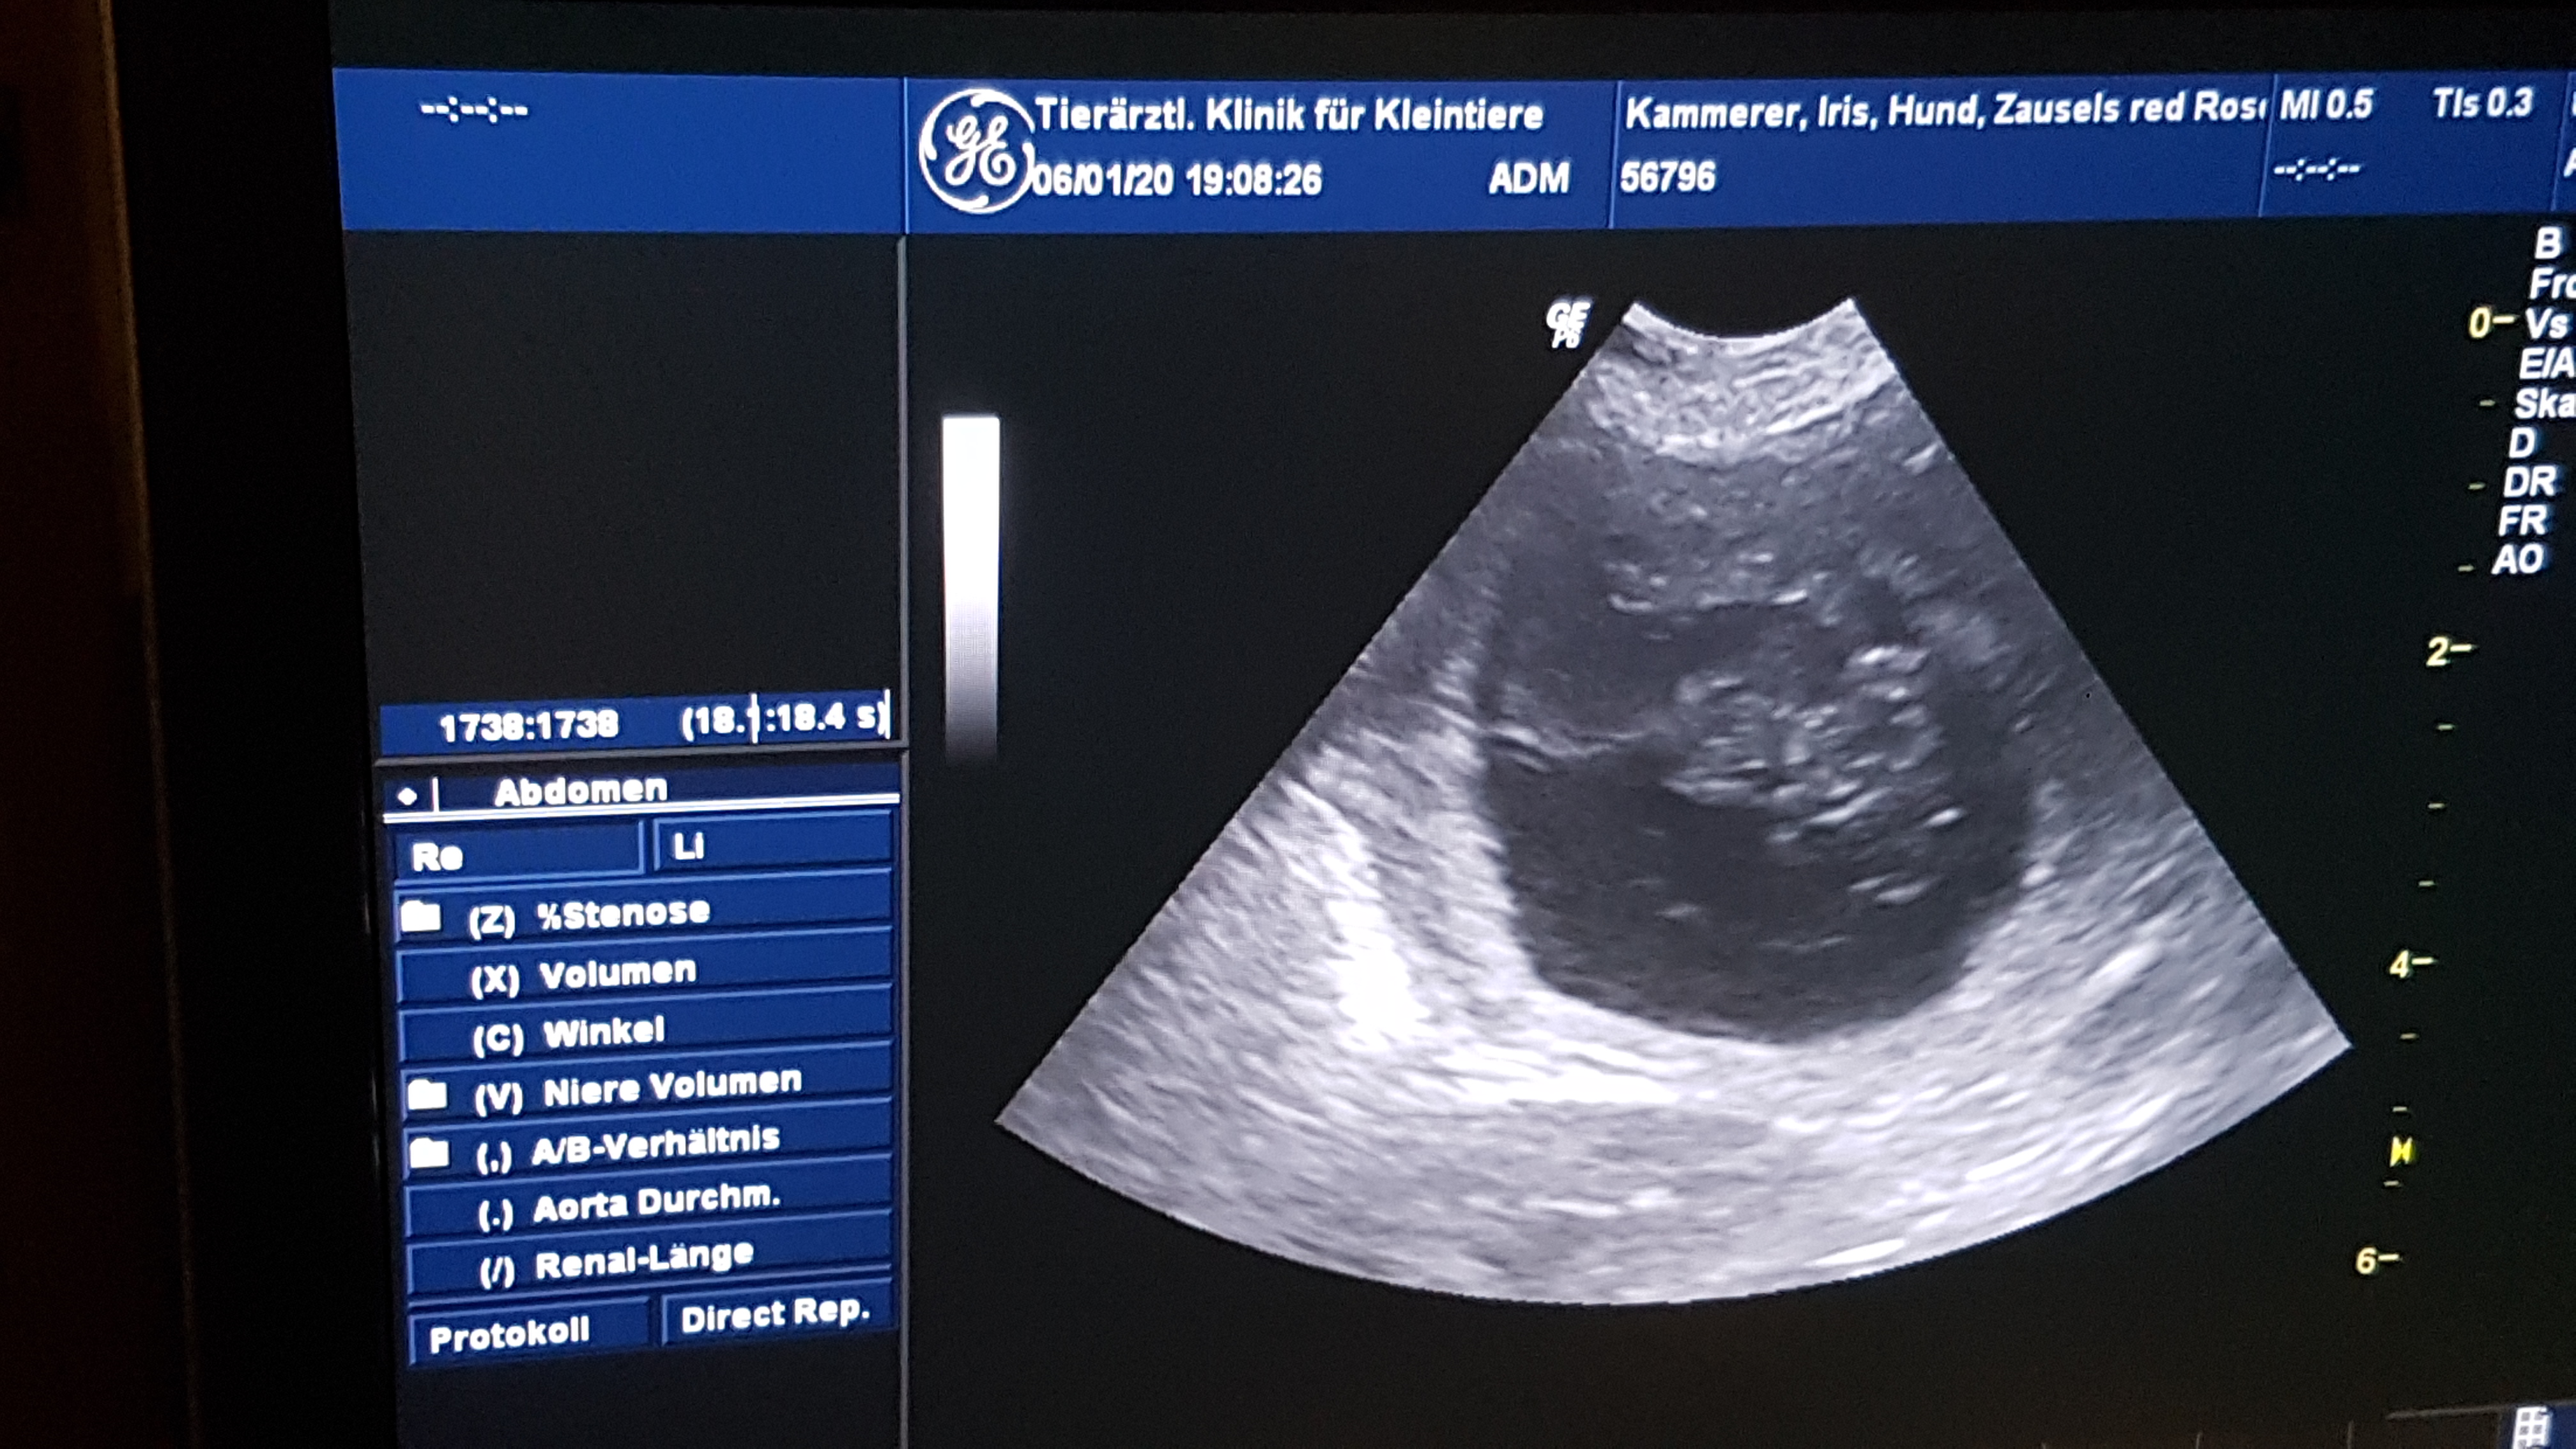

Einen Monat später stand fest, dass Kira aufgenommen hatte. Im Ultraschall wurden am Dreikönigstag 2020 fünf  Welpen entdeckt, deren Herzchen schlugen. Seitdem nahm Kira tüchtig zu und wurde sogar etwas milder im Umgang mit Opra, die sie sonst als Erzrivalin betrachtet.

6.1.2020 - Bestätigung im Ultraschall